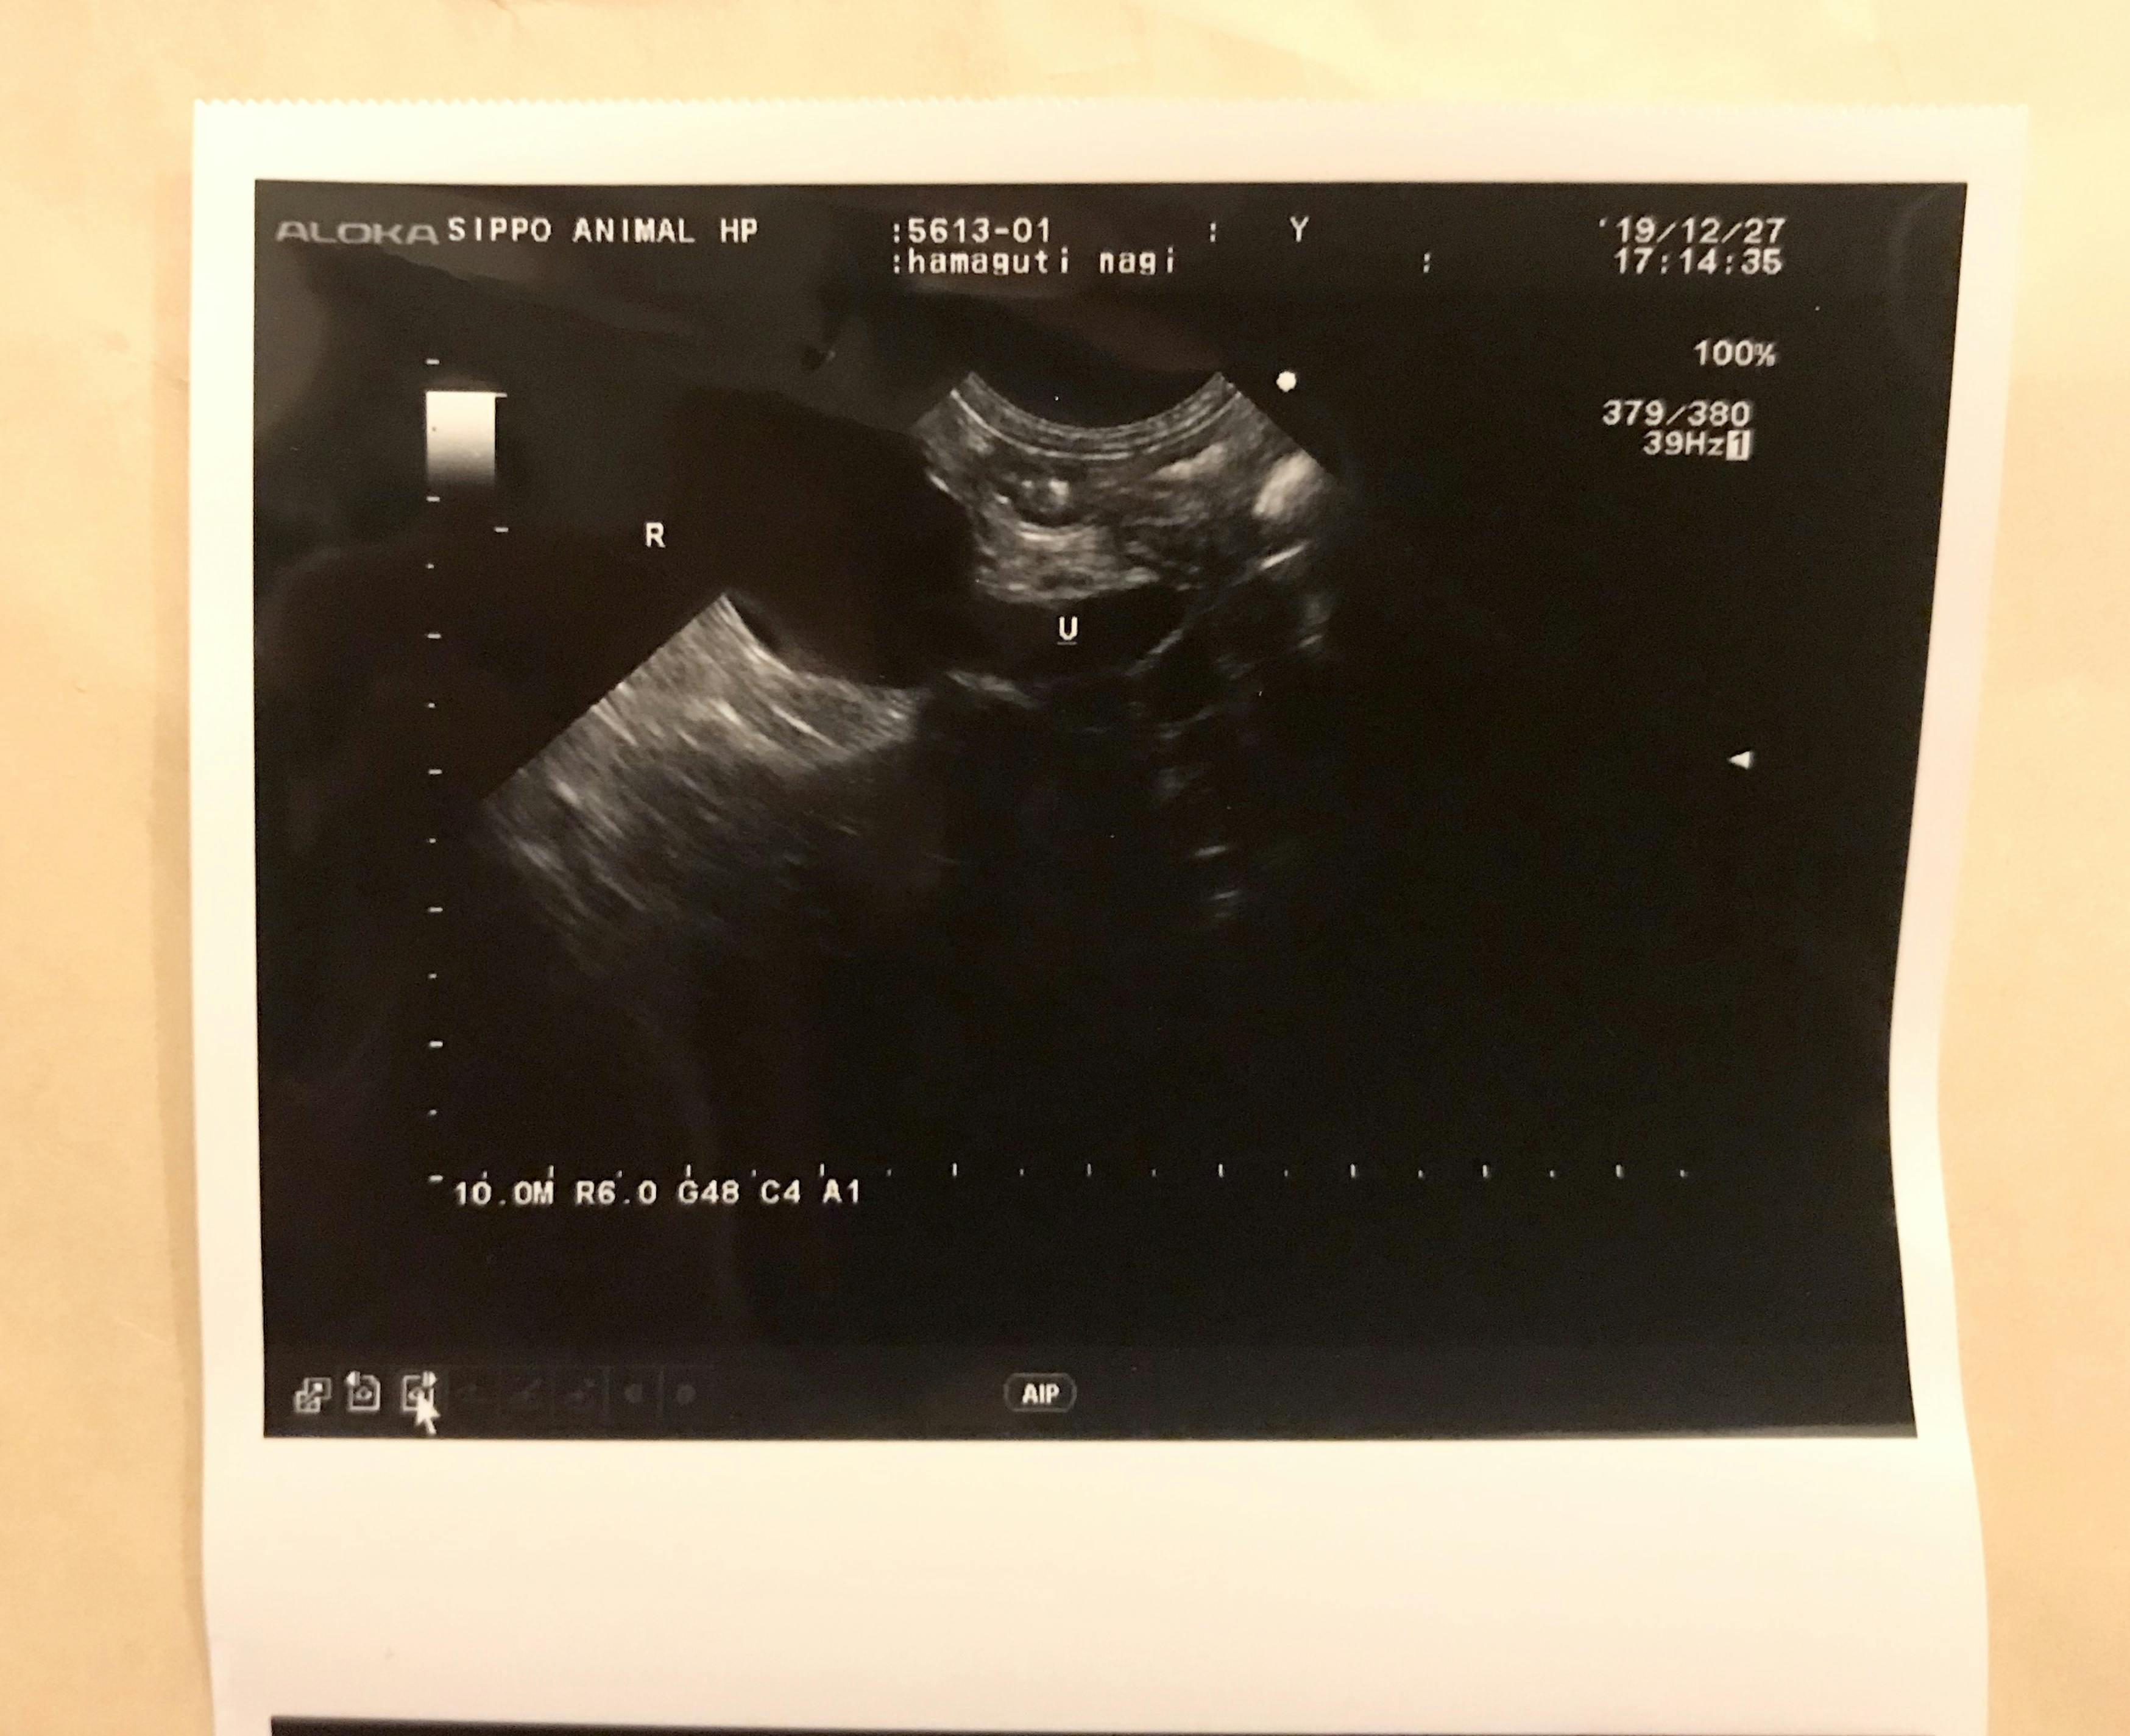

↓腎臓に尿がたまる水腎症も出ていると

エコーの写真で言われました。